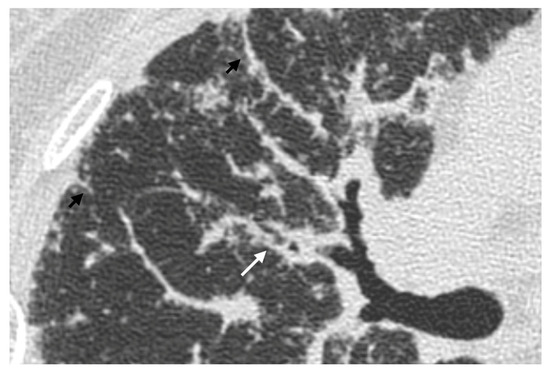

The Role of High-Resolution Lung Computed Tomography to Distinguish Between Fibrosing Hypersensitivity Pneumonitis and Usual Interstitial Pneumonia

by Dmitry A. Kuleshov, Svetlana Yu. Chikina, Galina V. Nekludova, Igor E. Tyurin and Sergey N. Avdeev

Background: Hypersensitivity pneumonitis (HP) is an interstitial lung disease (ILD) caused by repeated exposure to inhaled antigens in susceptible subjects. High-resolution computed tomography (HRCT) of the lungs is the leading diagnostic method for ILDs, but in some cases HRCT findings are not sufficient to distinguish HP and other ILDs, particularly, fibrotic HP (fHP) and usual interstitial pneumonia (UIP). Objective: The aim of this study was to develop HRCT criteria to diagnose fHP in patients with a UIP-like pattern. Methods: In this retrospective study, we analyzed HRCT scans of patients with fHP and a UIP-like pattern who underwent lung biopsy, and patients with idiopathic pulmonary fibrosis (IPF) and a UIP pattern in HRCT. Results: We included 51 patients with confirmed fHP and 24 patients with IPF/UIP in the analysis. IPF/UIP patients were older, were prevalently males, and did not have any systemic autoimmune diseases or risk factors for other ILDs. fHP patients were younger, with an equal number of males and females, and were more likely to be exposed to environmental antigens. HRCT abnormalities in the fHP group predominated in the lower lung areas or were diffuse in axial scans, whereas IPF/UIP patients mostly demonstrated a diffuse craniocaudal distribution and subpleural axial predominance. Centrilobular nodules and mosaic attenuation were present significantly more often in the fHP group; honeycombing, traction bronchiectasis, and emphysema prevailed in IPF/UIP patients. In the logistic regression analysis, patients with fHP and IPF/UIP differed in the presence of centrilobular nodules, honeycombing, and in both craniocaudal and axial distributions of HRCT abnormalities. In the ROC analysis, the combination of centrilobular nodules, honeycombing, and diffuse axial and craniocaudal distributions can predict the diagnosis of fHP (AUC, 0.953 ± 0.022; 95%CI, 0.910–0.995; p < 0.001). Mosaic attenuation and reticulation did not change the probability of fHP. Conclusions: The most significant HRCT features of fHP compared to the UIP pattern were centrilobular nodules, honeycombing, and a diffuse axial and craniocaudal distribution of abnormal findings. Reticulation, mosaic attenuation, and GGO do not increase the probability of fHP. Full article